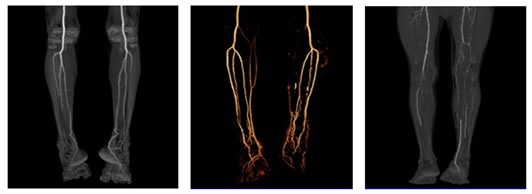

A total of 40 lower limb angiographic films were evaluated for the branching pattern of popliteal artery in the current study. The frequencies of terminal branching patterns of popliteal artery, in the present study population are summarized in Table 1.The normal level of popliteal arterial branching, usual pattern Type IA (with anterior tibial artery as its first branch followed by the tibioperoneal trunk which then subdivides into peroneal and posterior tibial arteries) was observed in 38 limbs (95%) Fig:1. Normal level of popliteal arterial branching -Trifurcation pattern, type IB was seen in 1 limb (2.5%) Fig:2. High division of popliteal artery, with anterior tibial artery being the first branch, arising above knee and having a normal course posterior to popliteus muscle, Type IIA1 was observed in 1 limb (2.5%) Fig:3.

Figure 1: Showing CT Angiogram of Type IA normal branching pattern of popliteal artery

Figure 2: Type IB- trifurcation of popliteal artery

Figure 3: Showing Type IIA1 -High division of popliteal artery